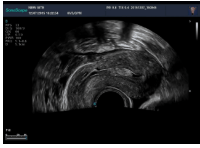

5腔內(nèi)探頭

腔內(nèi)探頭,具有頻率高,圖像分辨率高等特點(diǎn),不需充盈膀胱,探頭緊貼受檢部位,使盆腔器官處于聲束的近場(chǎng)區(qū)域,圖像更清晰。